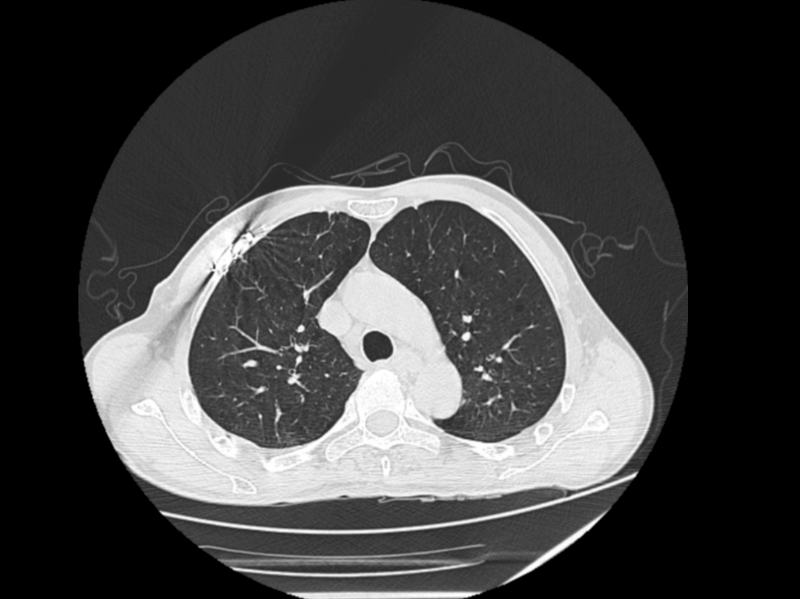

△治療后

手術(shù)當(dāng)日,王蕓帶領(lǐng)團(tuán)隊實施為薛先生手術(shù),先對右上肺、右下肺破裂傷進(jìn)行細(xì)致修補(bǔ),保障肺部功能恢復(fù);隨后開展右側(cè)第3-8肋骨骨折切開復(fù)位內(nèi)固定術(shù),憑借熟練操作完成骨骼精準(zhǔn)復(fù)位與固定;面對開胸后的出血,團(tuán)隊快速找到出血點并妥善止血。整個手術(shù)過程中,各環(huán)節(jié)銜接緊密,憑借醫(yī)護(hù)團(tuán)隊成熟的手術(shù)技術(shù)和豐富的臨床經(jīng)驗順利為薛先生完成手術(shù)。